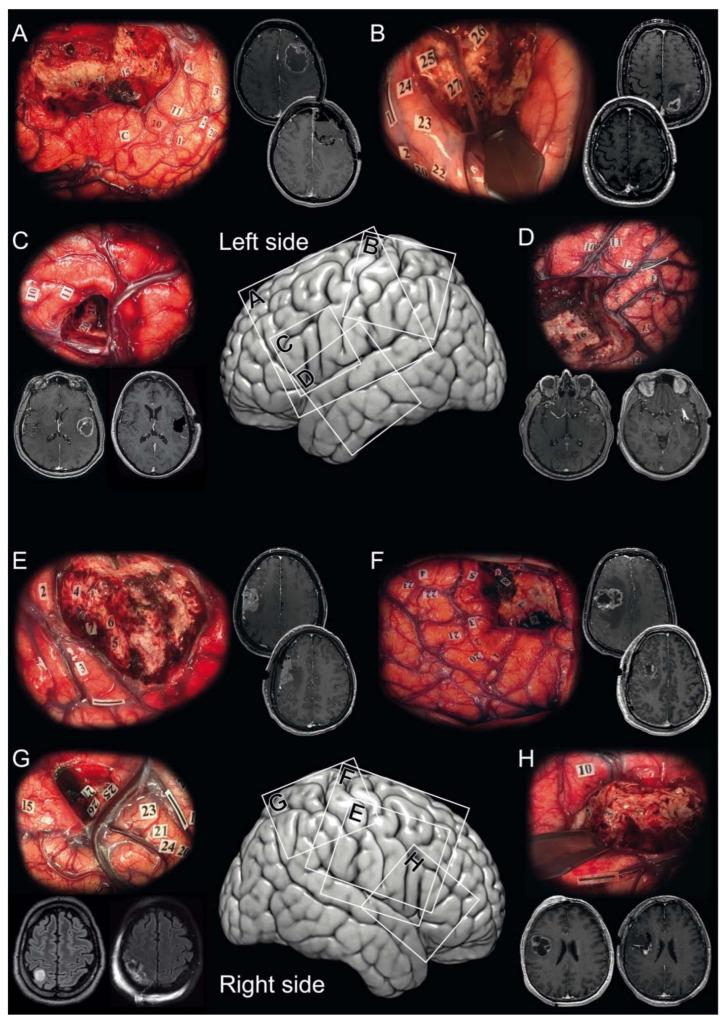

Feasibility, Safety and Impact on Overall Survival of Awake Resection for Newly Diagnosed Supratentorial -Wildtype Glioblastomas in Adults.

Although awake resection using intraoperative cortico-subcortical functional brain mapping is the benchmark technique for diffuse gliomas within eloquent brain areas, it is still rarely proposed for IDH-wildtype glioblastomas. We have assessed the feasibility, safety, and efficacy of awake resection for IDH-wildtype glioblastomas.

Observational single-institution cohort (2012-2018) of 453 adult patients harboring supratentorial IDH-wildtype glioblastomas who benefited from awake resection, from asleep resection, or from a biopsy. Case matching (1:1) criteria between the awake group and asleep group: gender, age, RTOG-RPA class, tumor side, location and volume and neurosurgeon experience.